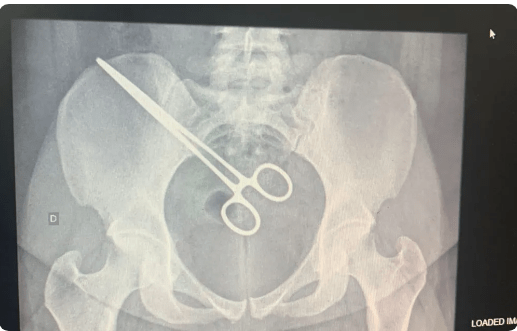

A mulher de 27 anos que passou mais de dois meses com uma pinça cirúrgica dentro do corpo descobriu que o objeto estava na região pélvica ao visitar o marido no Centro de Detenção Provisória (CDP) de São José do Rio Preto (SP).

Segundo a sogra da mulher, o detector de metais do CDP indicou que ela estava com algo metálico no corpo.

A sogra contou que, em setembro, a mulher fez uma cirurgia na Santa Casa de Araçatuba (SP) para retirada de um feto que estava sendo gerado nas trompas uterinas – que são dois canais finos responsáveis pelo transporte do óvulo, desde o ovário até a cavidade uterina.

Após o episódio no CDP, a paciente foi até a Santa Casa, onde fizeram um exame de raio X e constataram que a pinça estava dentro dela. A mulher foi internada novamente no hospital, na segunda-feira, para cirurgia de retirada do instrumento.

A Santa Casa informou que a paciente está estável, depois de passar pelo procedimento. A administração ainda reforçou que vai apurar se os protocolos foram seguidos pela equipe que realizou a cirurgia de retirada do feto.

“Ao final desta apuração, a direção do hospital tomará as medidas necessárias de responsabilização”, finaliza o hospital.

Fonte: G1 (Foto: Arquivo pessoal)